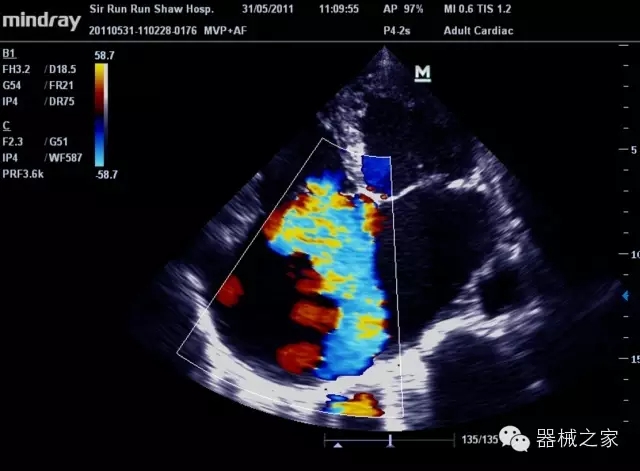

臨床圖片賞析